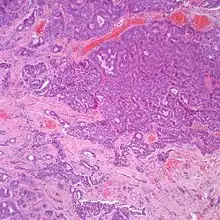

At the time of surgery, the tumor tends to peel away from the adjacent bones, although not the ossicles. It is usually fragmented, soft, rubbery and white to gray-tan. Due to the anatomic confines of the region, tumors are usually <1 cm.[8] The tumors arise below the surface, are unencapsulated, and have an infiltrative pattern of growth, composed of many different patterns (glandular, trabecular, cords, festoons, single cells). The tumor shows duct-like structures with inner luminal, flattened cells and outer, basal, cuboidal cells. The cells may have an eccentrically placed nucleus. The nuclear chromatin distribution is "salt-and-pepper", giving a delicate, fine appearance. Nucleoli are small with inconspicuous mitoses. There may be secretions in the gland tumor. It is possible to see a concurrent cholesteatoma.[2]